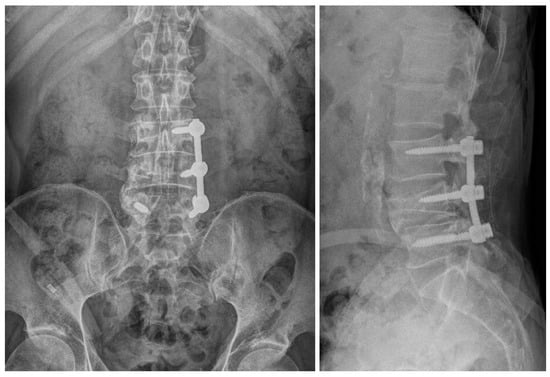

2.1. Case 1